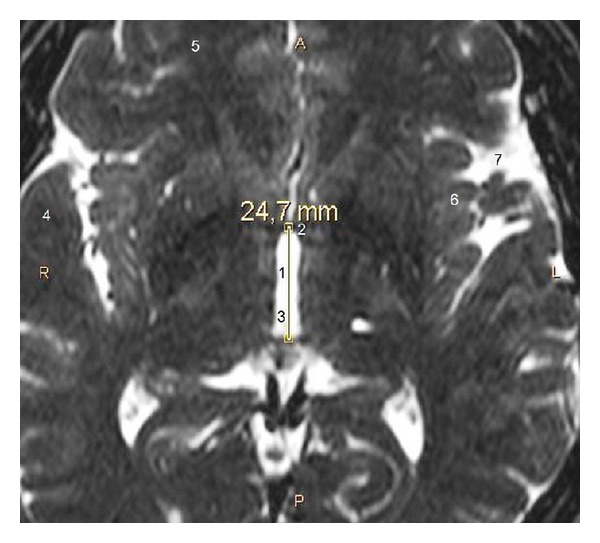

目的。我们的目的是提供一项以临床为导向的联合研究,重点研究人类STN的详细解剖结构,并在很大程度上考虑其靶向性。方法。在我们的成像研究中,我们使用了来自26名神经外科患者的脑磁共振图像(mri),并在我们的解剖研究中使用了来自18名尸体捐赠者的正常大脑的32个大脑半球。我们测量并分析了STN的尺寸(基于其立体定向坐标)。结果。在立体定向水平Z = -4时,mri上STN长度为7.7 mm,解剖标本上为8.1 mm。核磁共振成像宽度为6mm,解剖标本宽度为6.3 mm。MRI横切片平均可见STN 3.2片,最大尺寸为8.5 mm。mri上关节间距离26.3 mm,解剖标本上关节间距离27.3 mm。个体间STN的宽度和长度差异有统计学意义

Purpose. Our purpose was to provide a combined clinically oriented study focused on the detailed anatomy of the human STN, with great respect to its targeting. Methods. For our imaging study, we used cerebral magnetic resonance images (MRIs) from 26 neurosurgical patients and for our anatomic study 32 cerebral hemispheres from 18 normal brains from cadaver donors. We measured and analyzed the STN dimensions (based on its stereotactic coordinates). Results. At stereotactic level Z = -4, the STN length was 7.7 mm on MRIs and 8.1 mm in anatomic specimens. Its width was 6 mm on MRIs and 6.3 mm in anatomic specimens. The STN was averagely visible in 3.2 transverse MRI slices and its maximum dimension was 8.5 mm. The intercommissural distance was 26.3 mm on MRIs and 27.3 mm in anatomic specimens. We found statistically significant difference of the STN width and length between individuals <60 and ≥60 years old. Conclusion. The identification of the STN limits was easier in anatomic specimens than on MRIs and easier on T2 compared to T1-weighted MRIs sections. STN dimensions appear slightly smaller on MRIs. Younger people have wider and longer STN.